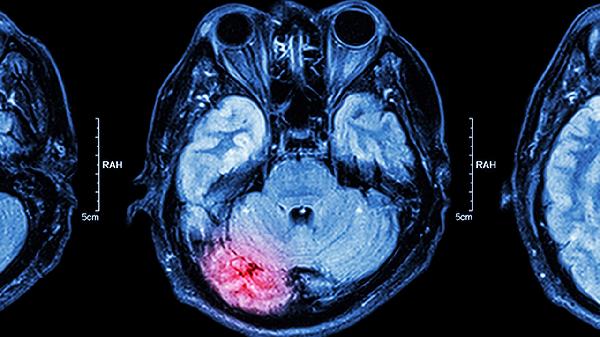

脑子充血是什么症状 脑子充血的四个症状揭秘

脑子充血通常是指脑部血管扩张或血流加速导致的头部不适感,可能与情绪激动、剧烈运动、高血压等因素有关,主要表现为头部胀痛、面部发红、头晕目眩、耳鸣等症状。建议及时就医排查病因。

日常应避免突然起身或剧烈转头,保持情绪平稳,限制钠盐摄入每日不超过5克。高血压患者需每日定时测量血压并记录,避免饮用浓茶或咖啡。若症状反复出现或伴随呕吐、意识障碍,须立即前往急诊科就诊,排除脑出血或蛛网膜下腔出血等急症。